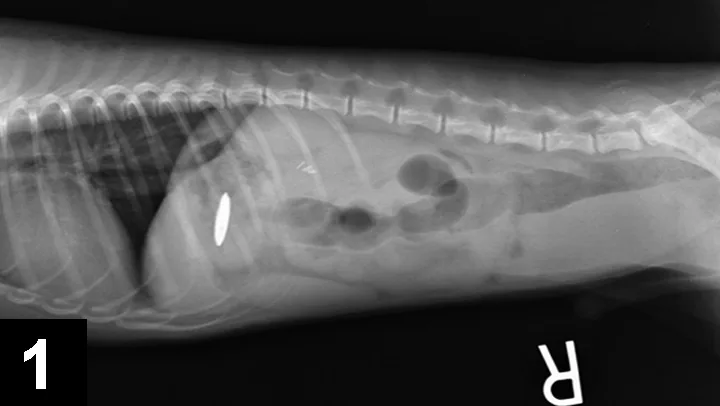

Abdominal radiographs (Figure 1) showed an apparently metal object in the stomach.

Figure 1. Radiograph showing foreign body.